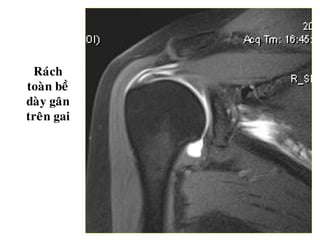

Raùch hoaøn toaøn gaân cô treân gai

Raùch

toaøn beà

daøy gaân

treân gai